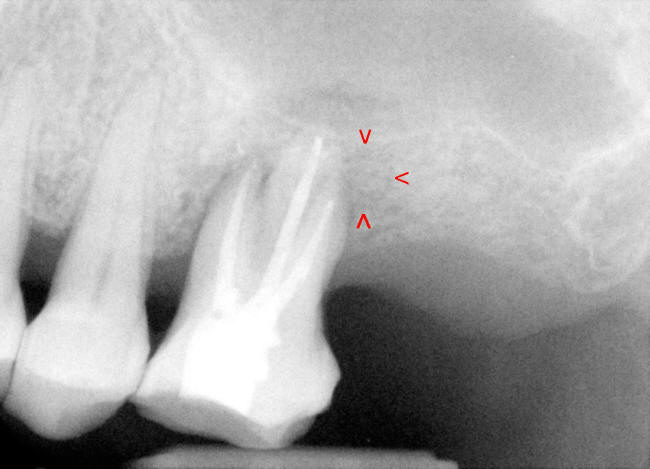

| 图一 术前根尖片左上6号牙根尖阴影阳性 | 图二 术前根尖片左上6号牙根尖阴影阳性 |

检查:面部对称,没有肿胀,没有牙关紧闭,口腔卫生尚可,多个修复物(补牙),左上7号牙缺失,左上6号没有蛀牙,牙龈退缩,4毫米牙周袋,轻度扣痛,没有窭道。根尖片(图一,图二)显示:左上6号牙骨质吸收,根尖有阴影。